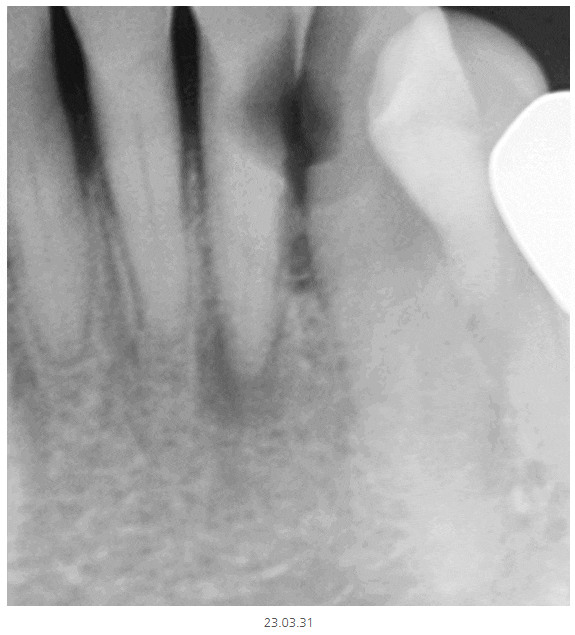

이럴 때 선택적으로 작은 x-ray를 촬영합니다.

부분적으로 확대하여 촬영하기 때문에

더 자세히 볼 수 있습니다.

정상적인 치아는 하얗게 속이 보이지만

충치가 파먹은 부분은

까맣게 나타나거든요~

텅~ 속이 비어있기 때문이죠.